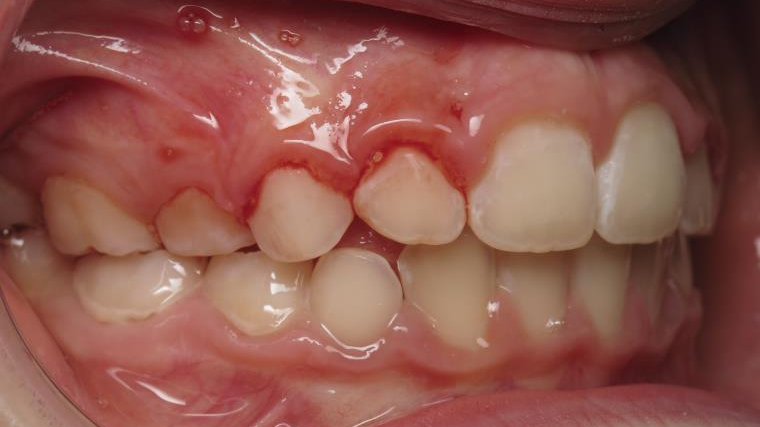

6 décalage sagittal 5 ans

Décalage entre les dents d avant en arrière

sectionnel multibagues